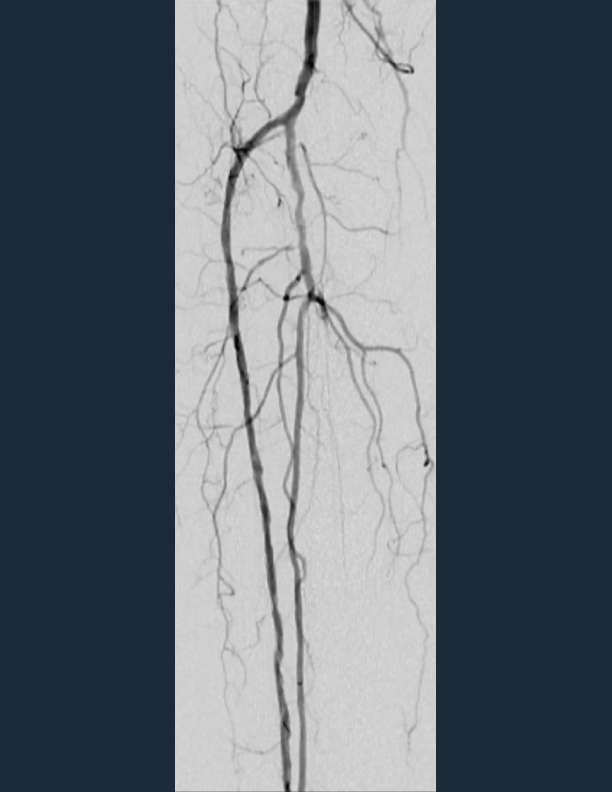

• angio during shockwave e8 treatment

400 pulses of Shockwave E8 delivered along ATA and < 10% residual stenosis across the lesion length